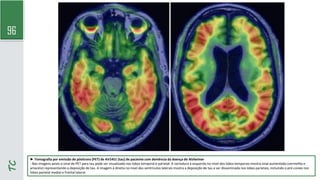

► Tomografia por emissão de pósitrons com

18fluorodesoxiglicose de paciente com demência da doença

de Alzheimer

- Reconstruções computadorizadas da proporção de captação

de glicose regional (usando a ponte como referência) da

superfície cortical mostram cores mais quentes (amarelo e

laranja) em áreas de captação normal de glicose, enquanto

cores mais frias (verde e azul) indicam hipometabolismo. A

imagem no topo é a de um indivíduo normal da mesma idade.

A imagem inferior é de um paciente com demência da doença

de Alzheimer típica e mostra hipometabolismo nas regiões

corticais temporal e parietal (setas).